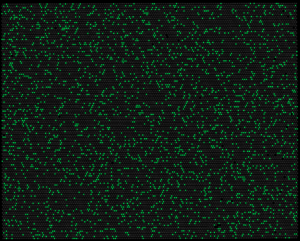

• Die Digitalisierung der PCR erfolgt durch die Verdünnung der cfDNA Moleküle/PCR-Templates in speziellen Mikrowellplatten. Im Optimalfall enthält jedes Well genau eine Zielkopie/PCR-Template.

• Während der PCR_Reaktion binden Fluorophor markierte Wildtyp- und Mutationsspezifische Sonden and die Zielregionen.

• Während der PCR-Reaktion werden die Fluorophore von den Sonden gelöst und geraten aus dem Einflussbereich des Quenchers.

• Nach dem Abschluss der PCR werden die Fluorophore bei spezifischen Wellenlängen zur Emission angeregt.

• Diese Emission wird über ein Kamerasystem auf den Analyseplatten detektiert und ergibt für jedes Mikrowell eine binäre Antwort (Signal Ja/Nein).

• Über eine Analysesoftware werden diese Signale ausgewertet und quantifiziert.